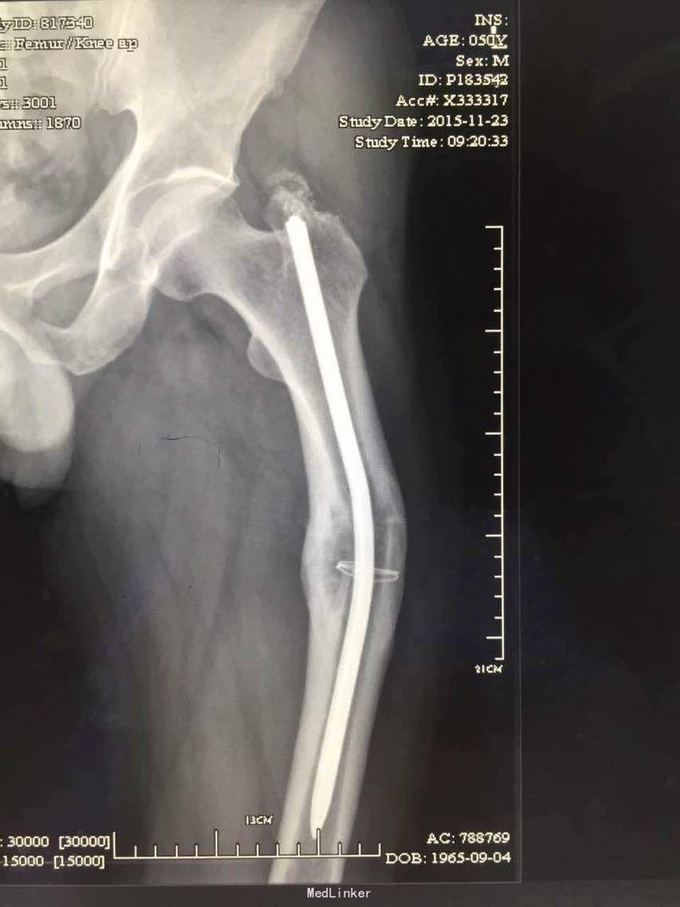

股骨骨折髓内钉固定取出

18年前股骨骨折髓内钉固定,骨折愈合1年半后拆内固定近端断裂失败,现在想再次手术拆除